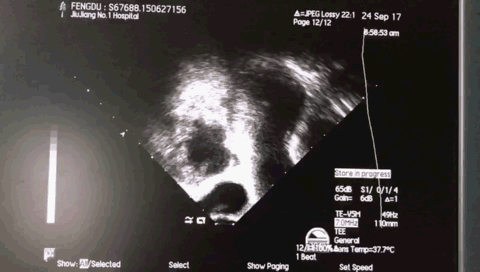

术前超声:

TEE 135: